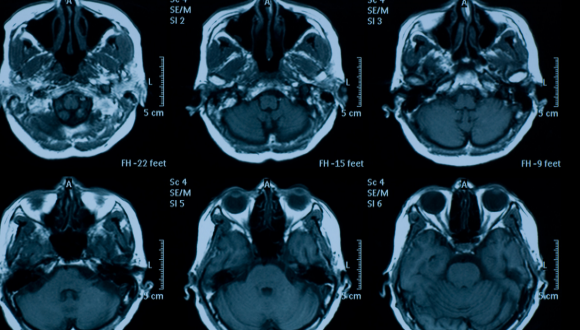

דימות | רדיולוגיה אבחנתית

בסמסטר ב' הקורס יתמקד בדימות ברפואה דחופה.